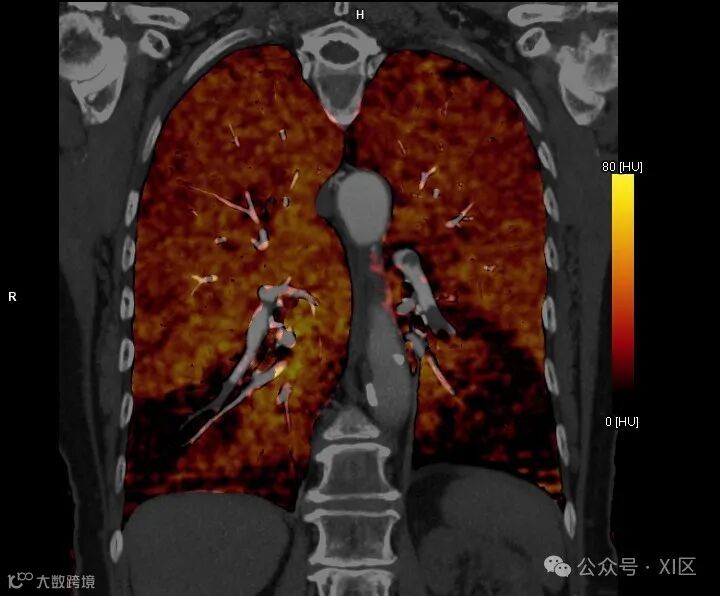

双能量CT(DECT)通过两种不同的X射线光子能谱来描绘组织的衰减特性,从而获取比单能量CT更丰富的物质组成信息。DECT生成的虚拟单色图像可用于提高对比噪声比并减少PE评估中的对比剂需求。DECT碘分布图可用于评价灌注缺损,研究显示其能够检测到CTPA上未见的额外段或亚段PE。 (更多内容参见XI区:双能量CT在肺栓塞中的应用) 。

此外,减影CT也是一种评估CTPA灌注的手段,通过从对比增强图像中减去预先采集的无增强图像来生成运动校正的碘分布图。加上碘图后,CTPA可更好地直观显示肺灌注,在一项研究中显示与DECT碘图相比,减影CT碘图在特异性上有小幅提升。然而,减影CT碘图的临床应用价值可能有限,且大规模前瞻性研究仍需进一步探索其在诊疗中的作用。